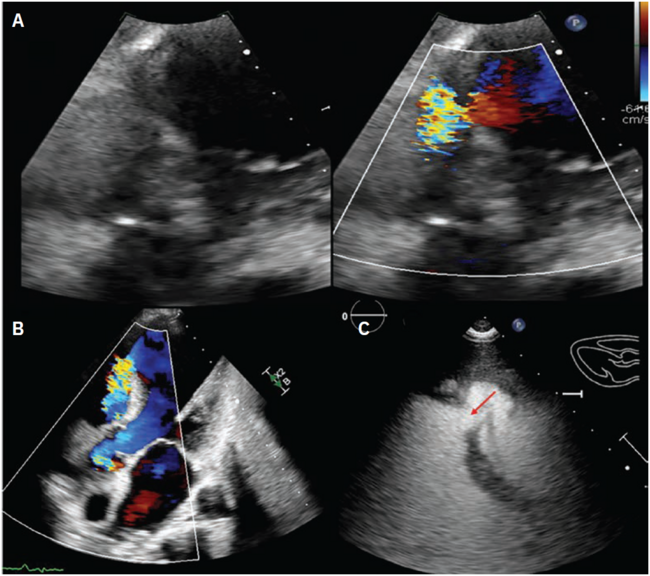

The final left ventriculogram showed no residual flow across the VSD (Video 3 [at end of case section]). Final echocardiographic images confirmed good position of the VSD occluder with no flow on color Doppler (Figure 3, Video 4 [at end of case section]). Right heart catheterization showed minimal step up in oxygenation (RA, RV, and PA saturation 68%, 72%, and 72%, respectively) with Qp:Qs 1.16:1.

Transthoracic and transesophageal echocardiography after VSD closure showing well-seated occluder with no flow on color Doppler.

VSD = ventricular septal defect